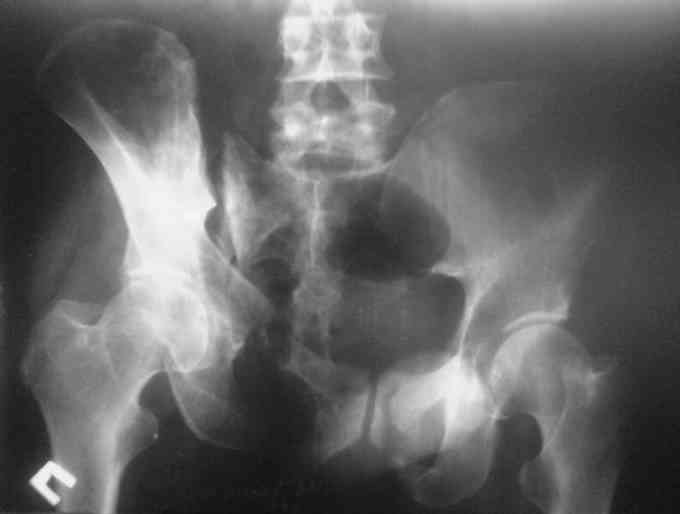

Остается только вариант закрытого аппаратного лечения. В аттаче положение отломков на вытяжении в прямой (АР) проекции. Для сравнения снимок до и во время вытяжения.

> Остается только вариант закрытого аппаратного лечения.. В аттаче

> положение отломков на вытяжении в прямой (АР) проекции. Для сравнения

> снимок до и во время вытяжения.

Только аппаратными методами в этом случае проблему не решить (фактически вы имеете дело с болтающимися псевдоартрозами), потребуется открытое вмешательство.

Первоочередно для тазовых операций важно обследование, снимки таза в инлет, оутлет и прямая

проекция.

На сравнительном снимке правый полутаз опустился

недостаточно, можно добавить вес и сделать все стандартные снимки.